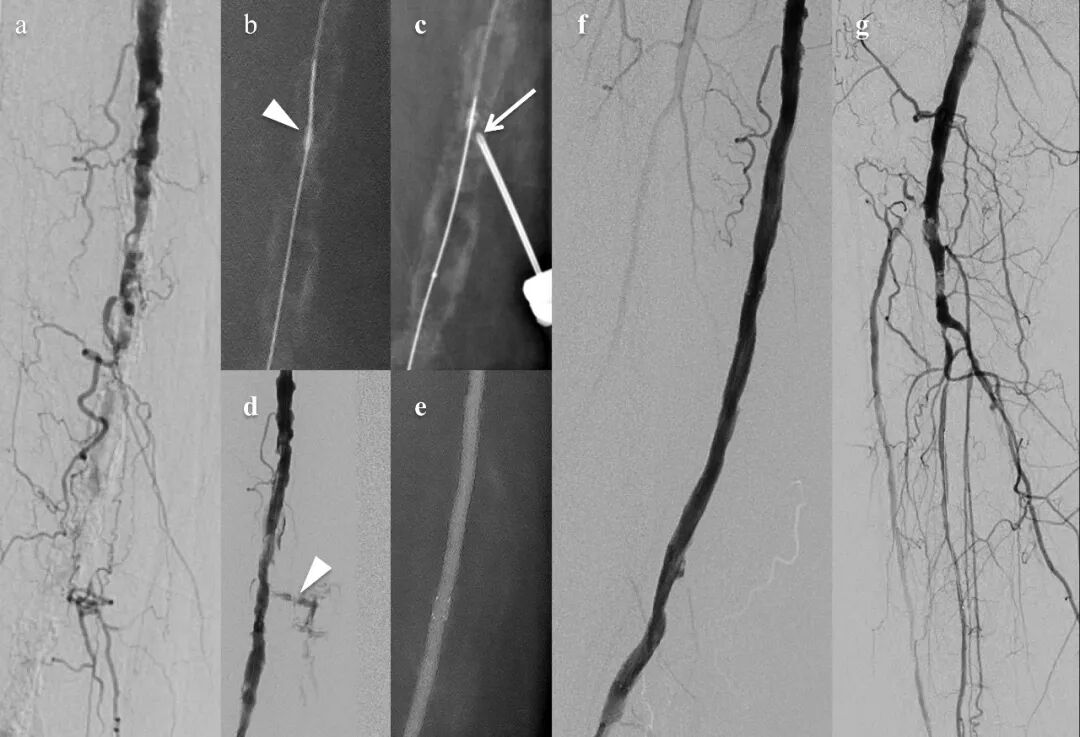

原文图2. 经皮直接钙化斑块穿刺(PIERCE)技术及其改良术式。(A)直接PIERCE技术:经皮穿刺针刺入钙化斑块以辅助球囊或导丝通过。(B)BECOST技术:在张力性穿通导丝上使用钝头针裂解钙化病变。(C)会师-PIERCE技术:逆行针穿过重度钙化向顺行导丝方向钻入。(D)BAMBOO SPEAR技术:弯曲的裸金属针钻入联合辅助球囊血管成形术。(E)活检钳技术:机械性切除钙化斑块。BAMBOO SPEAR:针钻法;BECOST:张力性穿通导丝上钝性内膜下开裂。

原文中央插图. 复杂钙化外周动脉疾病(PAD)的先进针具策略。针对常规导丝通过或球囊扩张失败的严重钙化PAD病变,采用基于针具的斑块修饰技术的示意图。BAMBOO SPEAR:针钻法;BECOST:张力性穿通导丝上钝性内膜下开裂;DECIAP:钳夹诱导动脉斑块开裂直接内膜切除术;IVL:血管内碎石术;PIERCE:经皮直接钙化斑块穿刺。